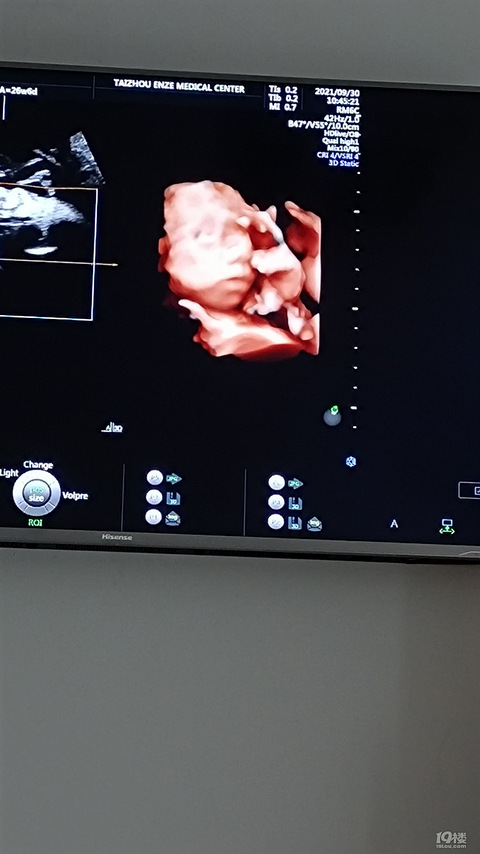

起什么标题好呢?【2021孕妈日记】

预产期:2022年1月20日建卡医院:椒江区妇幼保健所产检医院:28周前妇幼保健所,之后市立医院胎宝宝小名:生产医院:市立医院附三维B超照片:电梯备孕计划好孕心情打发时间一孕妈建档早唐和NT中唐糖耐和三维大排畸准生证第一次胎心监护33+5 周住院保胎懒妈的囤货38+2破水产娃宝宝秀产后修身